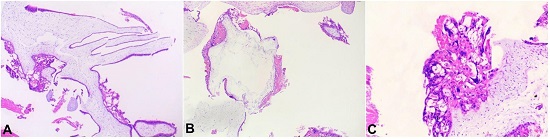

The histopathology study of the normal-looking placental part showed normal villi and sinusoids. The histology of the molar area revealed enlarged villi with hydropic change. The hydropic villi exhibited prominent invaginations, cisterns, and extensive circumferential trophoblastic proliferation (

Figure 3). Sections drawn from the central part of placenta revealed a dividing membrane between the normal placenta and the villous part (

Figure 3

Photomicrographs of the placenta showing in A, B, and C – Hydropic avascular villi with cisterns and trophoblastic hyperplasia.